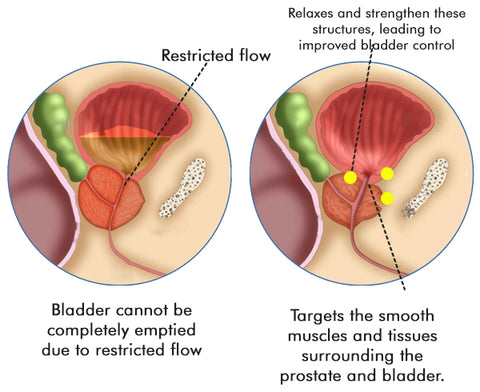

How does it work?

Lancetswell™ Saw Palmetto Prostate Health Supplement are meticulously crafted to provide comprehensive support for prostate health and alleviate the bothersome symptoms often associated with prostate issues.

Reducing Inflammation: Prostate problems are frequently linked to inflammation within the prostate gland. The capsules contain a unique blend of natural compounds renowned for their potent anti-inflammatory properties. By targeting and reducing inflammation in the prostate, these capsules help alleviate pain, discomfort, and swelling associated with prostate issues. Interferes with the production or activity of inflammatory mediators, such as cytokines and prostaglandins. By doing so, they help modulate the inflammatory response, resulting in a decrease in inflammation and swelling.

Enhancing Urinary Function: Frequent nighttime urination is a common symptom experienced by individuals with prostate issues. Lancetswell™ Prostate Health Capsules specifically target the smooth muscles and tissues surrounding the prostate and bladder. Through their action, these Capsules relax and strengthen these structures, leading to improved bladder control, reduced urinary urgency, and a healthier urinary flow. This ultimately results in fewer nighttime trips to the bathroom.